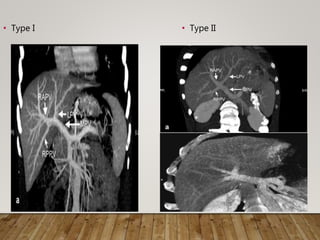

• Type I • Type II

TYPE III PORTAL VEIN

• Significantly Lower

ERLV

• 31% have ERLV < 30%

• If RAPV arises in the

umbilical fissure, the

course is intrahepatic

and may be injured

• Requires either double

reconstruction or back

table reconstruction